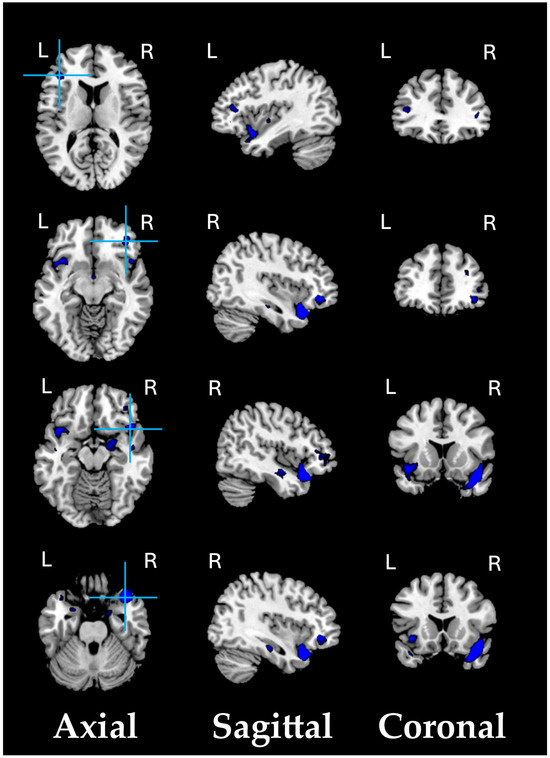

3.5. Post Hoc Analysis of ROI-GMV and Selected GP Items

As the post hoc analysis of PANSS scores for GP items revealed that a specific cluster of mood-related symptoms primarily contributed to the GP scale, we decided to further investigate the association between this cluster of symptoms and the VBM-GMV, which was significantly associated with the severity of the GP scale. We defined a region of interest (ROI) centered on the right ITG, specified as a 6 mm radius sphere (BA 20; MNI coordinates: 61, −26, −28). Four significant positive associations were found between the ROI and the following: GP02—Anxiety scores (t = 3.89, p = 0.0002, q < 0.01, Cohen’s d = 0.910), GP05—Mannerisms and posturing scores (t = 3.89, p = 0.0002, q < 0.01, Cohen’s d = 0.910), GP06—Depression scores (t = 4.43, p = 0.00003, q < 0.01, Cohen’s d = 1.037), and GP09—Unusual thought content scores (t = 4.24, p = 0.00006, q < 0.01, Cohen’s d = 0.992). As shown in Figure 3, the greater the VBM-GMV in the right ITG, the more severe the levels of anxiety and depression (panels A and C), the more bizarre or disorganized the movements and posture (panel B), and the more strange, fantastic, or bizarre the ideas and thought content (panel D).

Figure 3.

Correlation plots showing significant relationships between the VBM-GMV in the right inferior temporal gyrus (ITG) and the items contributing the most to the Generalized Psychopathology PANSS subscale in SZ patients (q < 0.01).

Compared with HC participants, SZ patients’ VBM-GMV at the ROI level tended to be reduced, pointing to overall atrophy of the right ITG (details in Figure S1, in the Supplementary Materials).

The following supporting information can be downloaded at: https://www.mdpi.com/article/10.3390/biomedicines13030736/s1, Figure S1. The ROI-based GMV post hoc analysis revealed that, compared with 91 HC participants, 74 SZ patients’ VBM-GMV at the ROI level tended to be reduced (p < 0.01 FDR-corrected).